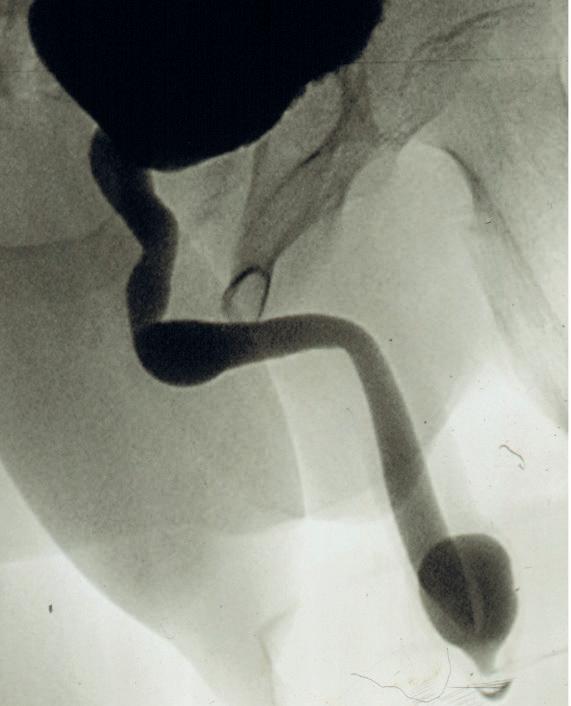

Abb. 1: Phimose. Abb. 2: Vesikoureteraler Reflux – prä- und postoperative Miktionszystourographie nach Ostiumunterspritzung.

Bei Verdacht auf infravesikale Obstruktion sowie nach fieberhaften rezidivierenden symptomatischen Harnwegsinfektionen sollte eine spezielle weiterführende kinderurologische Diagnostik mit Miktionszystourographie (MCU), Uroflowmetrie und Urethrozystoskopie in einer spezialisierten Klinik für Kinderchirurgie/Kinderurologie erfolgen. In einigen Fällen können die Ursachen des „Harnverlierens“ nur durch einen operativen Eingriff behoben werden. Bei Vorliegen eines vesikoureteralen Refluxes ist das Ziel der Behandlung der Schutz der Nieren vor Infektionen und Parenchymabbau. Nach Möglichkeit soll unter konservativer Therapie (antibiotische Harnwegsinfektprophylaxe) eine Maturation, also die Verstärkung der fibromuskulären Strukturen der Blase, abgewartet werden. Die Indikation zur Art der Behandlung ergibt sich vor allem aus dem Refluxgrad, dem Alter des Kindes und der Entwicklung der renalen Funktion. Neben der konservativen Behandlung kann ohne viel Aufwand die endoskopisch submuköse Ostiumunterspritzung durchgeführt werden (siehe Abbildung 2). Viele Patienten mit kindlicher Harninkontinenz werden über einen langen Zeitraum erfolglos als Bettnässer behandelt, und das eigentliche zugrundeliegende Problem ist noch nicht einmal diagnostiziert worden. Die „vorschnelle“ Gabe eines Medikamentes ohne vorausgegangene kinderurologische Abklärung ist strikt abzulehnen.